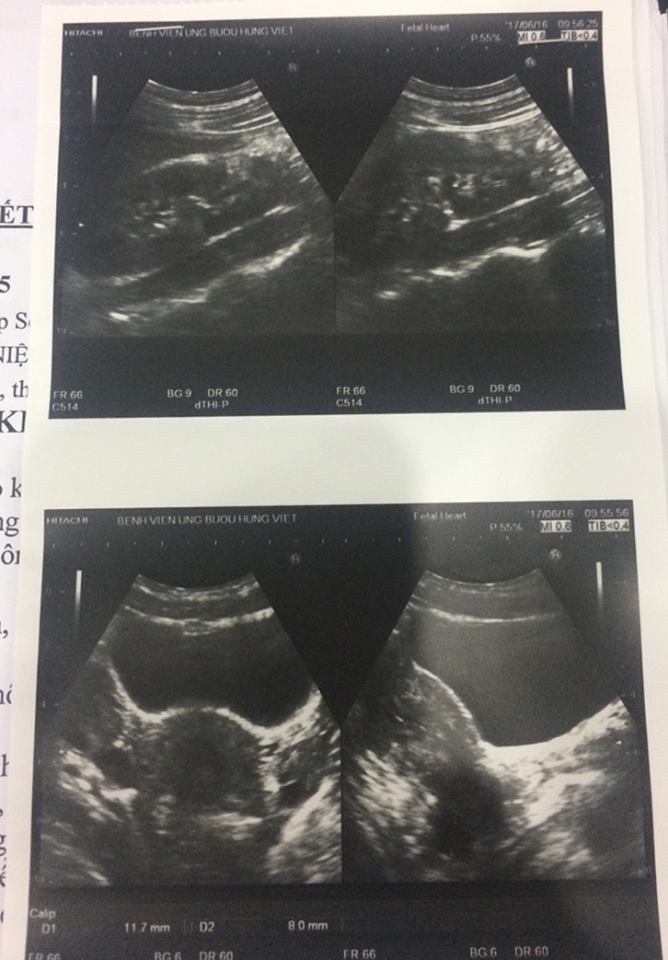

Hình ảnh vùng thận của bệnh nhân sau khi đã được phẫu thuật. Ảnh: Bác sĩ cung cấp.

Tại Bệnh viện Ung bướu Hưng Việt, sau khi thăm khám kỹ càng và có được kết quả sau khi chụp cắt lớp vi tính, bác sĩ Nguyễn Sĩ Tiến - khoa Khám bệnh - nhận thấy bệnh nhân Phương bị dị tật bẩm sinh niệu quản, có một thận phụ và đề nghị tiến hành phẫu thuật ngay lập tức.

Bác sĩ Lê Thanh Hải - người điều trị trực tiếp cho bệnh nhân Phương - cho biết đây là ca bệnh khá đặc biệt khi người bệnh có tới 3 thận, 3 niệu quản. Người có ba quả thận rất hiếm gặp. Nếu các thận hoạt động bình thường sẽ không ảnh hưởng đến sức khỏe bệnh nhân.

Tuy nhiên, với trường hợp của Phương, thận phụ phải teo nhỏ, chức năng đã hạn chế đi rất nhiều và có dấu hiệu ứ nước nên cần loại bỏ ngay. Những trường hợp không phát hiện sớm để cắt bỏ dị tật này có thể gây mất chức năng thận, làm bệnh nhân hay bị viêm nhiễm, thậm chí sẽ ung thư hóa.